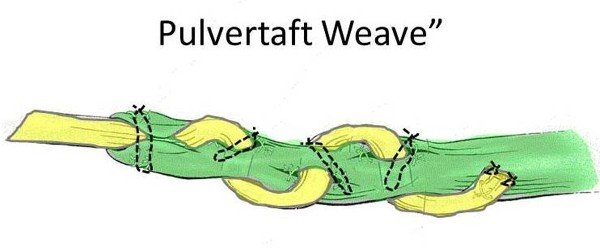

2. EI to EPL tendon transfer.

- The Extensor Indicis (EI) tendon (used to extend the index finger) is redirected to take over the function of the EPL.

- The thumb and wrist are protected in a cast for 6 weeks.

- The transfer is intentionally made “tight” because it tends to stretch over a period of weeks. When you first come out of the cast you will be convinced that the thumb will “never move again”. It will. By 10 - 12 weeks most patients have full motion.